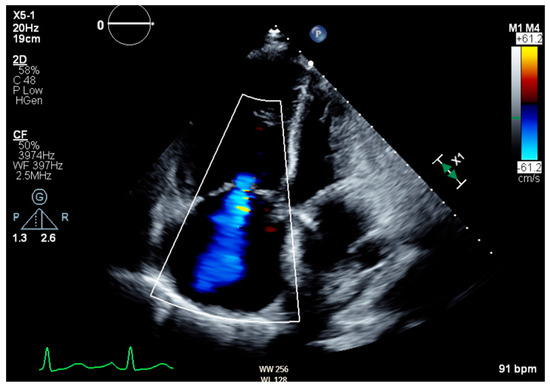

Notable normal admitting lab values included the following: aspartate aminotransferase, alanine transaminase, alkaline phosphatase, bilirubin, platelet count, and international normalized ratio. Creatinine on arrival was 0.79 mg/dL and white blood cell count was 6.0 cells/μL. The only noteworthy abnormal lab was an elevated brain natriuretic peptide of 864 pg/mL. Venous blood gas on arrival with pH of 7.353, pCO2 55.9 mmHg, HCO3 31.1 mmHg, and pO2 21 mmHg. Large-volume paracentesis was performed (5 L), with fluid analysis revealing a serum–ascites albumin gradient (SAAG) of 1.2 g/dL and total protein of 2.6 g/dL. The total nucleated cell count was 1020 cells/mm3 with a polymorphic nucleated cell count (PMN) of 663 cells/mm3, consistent with SBP. The bacterial culture of peritoneal fluid did not grow any organism. An abdominal ultrasound revealed nodular contours within the liver and heterogeneous echotexture compatible with cirrhosis (Figure 1). Doppler imaging of the liver showed patent vessels. Repeat TTE on this admission showed a preserved EF of 65% with paradoxical septal motion, flattened interventricular septum, and severe right ventricular (RV) enlargement consistent with RV pressure/volume overload. The pulmonary systolic pressure was estimated at 74 mmHg (Figure 2). Additionally, the patient was found to have moderate tricuspid regurgitation with a maximum velocity of 385 cm/second (Figure 3).

Figure 3. Transthoracic echocardiogram in apical four-chamber view showing moderate tricuspid regurgitation with a maximum velocity of 385 cm/second and max pressure gradient of 59.3 mmHg.